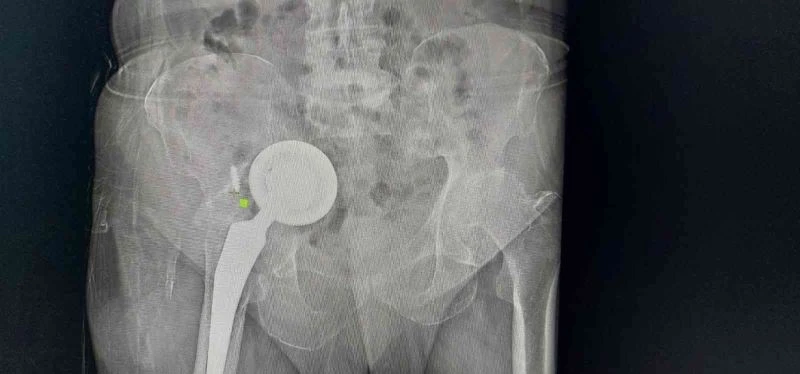

Yıllarca ağrılarından rahatsız olan 74 yaşındaki Ömer Demir, geçirdiği iki kalça protezi operasyonu sonrası doktorların gerekli bulmasına rağmen yeniden ameliyat olmak istemeyince kalçasındaki protez vücudunda hareket etmeye başladı. Baş kısmı karnından diğer parçası bacağından çıkarılan protezle ilgili konuşan Demir, "Neredeyse karnına girecek’ dediler, benim tuhafıma gitti. Protez buradan çıksa gelip karnıma girse farkında olmam mı dedim, ameliyat olmadım. Şu an Allah’a şükür, yürüyorum, ameliyat olduğum bacağımda hiç sorun yok, doktorlarıma güveniyorum” dedi.

Adıyaman’da yaşayan 74 yaşındaki Ömer Demir, geçtiğimiz yıllarda kalça bölgesinde hissettiği rahatsızlıklar sonrası doktora gitti. Kalçasında kireçlenme olduğu belirlenen Demir, kalça protezi ameliyatıyla şikayetlerinden kurtuldu. Edinilen bilgiye göre zaman içerisinde yeniden ağrılar hissederek hastaneye başvuran Demir’in protezine revizyon ameliyatı yapıldı. Ancak bir süre sonra yaşlı adamın ağrıları yeniden kendini gösterdi ve uzmanlar operasyon gerekliliğini ifade etti. İddiaya göre geçirdiği operasyonlar sonrası tekrar ameliyat olmak istemeyen Demir, gittiği birçok doktoru dinlemedi, protezi ise karın içi ve uyluk kemiğinde ilerlemeye başladı. Zamanla ağrıları dayanılmaz hale gelen yaşlı adam, en son Başakşehir Çam ve Sakura Şehir Hastanesi’ne geldi. Burada yapılan tetkikler sonrası protezin diğer organlarını olumsuz etkileyecek şekilde vücudunda ilerlediğini duyan yaşlı adam, ameliyata onay verince acil şekilde operasyona alındı. Başakşehir Çam ve Sakura Şehir Hastanesi Ortopedi ve Travmatoloji Uzmanları Dr. Mustafa Özçamdallı ve Dr. Necati Doğan’ın ekipleriyle gerçekleştirdiği operasyonla protezin üst kısmı karın içinden alt kısmı ise hastanın bacağından çıkarıldı. Yeni protez ise başarılı bir şekilde bölgeye yerleştirildi. Hastada yaşanan durumla çok sık karşılaşmadıklarını ifade eden Uzm. Dr. Özçamdallı ve Doğan tedaviye ilişkin bilgi verirken Demir, yaşadıklarını anlattı.

Demir’in geldiği pozisyonu ve uyguladıkları tedaviyi anlatan Dr. Necati Doğan, “Hastamıza yıllar önce kalça kireçlenmesi nedeniyle kalça protezi uygulanmış, bu protez uygulamalarında sıklıkla başarılı sonuçlar elde ederiz. Daha önce gittiği hastanelerde bu protezin yenilenmesi gerektiğini hastamıza söylemişler. Hastamız o anki risklerden dolayı bu süreci kabul etmemiş, ötelemiş ve yaklaşık 2-3 yıl boyunca bu protezi kullanmaya devam etmiş. Protezde ilerlemeye devam etmiş. Bize başvurduğunda artık protez karın içindeki organların arasına kadar yerleşmişti. Bacakta ciddi şişlikleri, hareket kısıtlılıkları oluşmuş, yürüyemez hale gelmişti. Yenileme ameliyatı gerektiğini söyledik ve hastamız artık mevcut tablosundan ileri derecede şikayetçi olduğu için belirli riskleri, ameliyatı kabul etti. Protezin bu kadar ileriye gitme aşaması sık karşılaştığımız bir şey değil, daha erken evrelerde geldiklerinde sadece kalça bölgesi açılır. Daha uyumlu protezlerle kalçadaki implant değiştirilir ve hayatına geri döner. Ama bu hastamız artık normal bölgeden çıkarılamayacak derecede ilerlemiş formuyla geldiği için bizim bu protezi kalça bölgesinden çıkarıp onarmamız imkansızdı. İlk olarak karın içindeki kısımları çıkartmak için karın bölgesinden girdik. Protezin yuva baş dediğimiz kısımlarını karın içinde mesanenin, bağırsakların, damar sinir paketlerinin arasından güvenli ve sorunsuz bir şekilde çıkarttık. Daha sonra bu kemikte oluşmuş ileri derecedeki defekti de onarmak gerekiyordu, buraya da uygun platinlerle tekrardan yeni yapılan protezler içeri gelmesin diye yeni platinlerle bir destek kısmı oluşturduk. Karın iç kısmındaki işimiz bitti daha sonra ikinci bir aşamada kalça bölgesinde kalan kısmı çıkarttık. Şu anki protezimiz gayet stabil ve hemen hareket etmeye, yük vermeye, yürümeye uygun bir protez. Vatandaşların protezlerini düzenli takip ettirmeleri gelişen herhangi bir yeni şiddetli ağrı ve problemlerde mutlaka en erken dönemde bu aşamalara gelmeden kontrollerini yaptırmalarını öneririm" dedi.

Protezin üst kısmının karın içinden alt kısmının ise bacaktan çıkarıldığını ifade eden Ortopedi ve Travmatoloji Uzmanı Dr. Mustafa Özçamdallı, “Hastamız bize geldiğinde yürüyemez bir vaziyetteydi daha önce birkaç kez operasyon geçirmiş ve protezi karın dediğimiz boşluğa kadar ulaşmış durumdaydı. Hastanın damarlarında ve sinirlerinde hasarlar meydana getirebilecek seviyedeydi. Özel dizayn edilmiş kafes dediğimiz protezlerle ve daha uzun revizyon dediğimiz protezlerle hastamızın operasyonunu başarılı şekilde gerçekleştirdik. Böyle durumlar hastaların ilerleyen dönemlerinde dolaşımını bozup bacaklarımı kaybetmeye kadar gidebilir. Bu hastamızda ek birtakım rahatsızlıklar olması sebebiyle diyabet, kalp rahatsızlığı, sebebiyle yatağa bağımlı olması bu hastalarda mortalite dediğimiz durumu arttırmaktadır. Bu çok sık karşılaştığımız bir hasta grubu değil. Kesinlikle kalça protezi yapılan hastalarımızın kontrollerine rutin olarak gitmeleri gerekir. Bu hastamız biraz operasyonlardan çekinmiş ve birkaç operasyona girince, çok yüksek olduğu anlatılınca korkmuş ve dolayısıyla bu şekilde hayatını bir 3-4 yıl daha idame ettirince protezin daha da aşınıp leğen kemiğinin yukarısına doğru çıkmasına sebep olmuş. Kendisine ameliyat önerilmesine rağmen ameliyatlarını kabul etmemişti ve bu protez leğen kemiğinde aşınmaya sebep olup karın içi organlara kadar ilerlemiş vaziyetteydi. Biz protezi 2 parça halinde çıkarttık. Protezin üst kısmını karın bölgesinden, alt kısmını uyluk kemiğinden çıkarttık" diye konuştu.